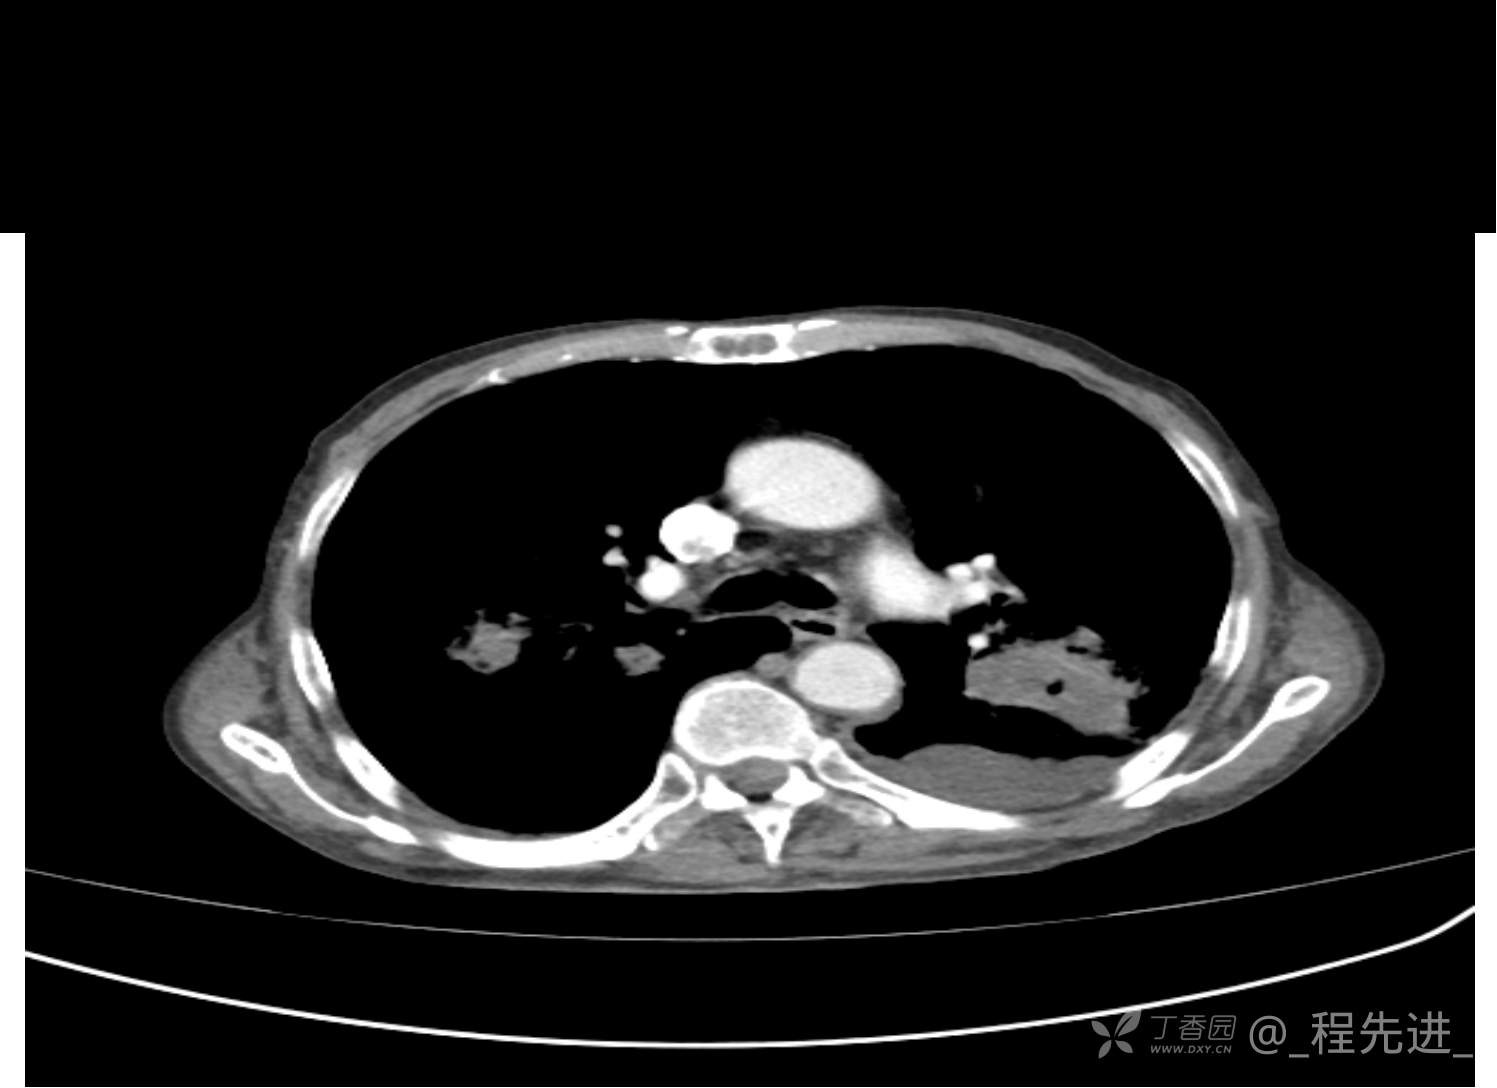

患者性别:男

患者年龄:81岁

简要病史:反复咳嗽、咳痰20余年,加重1周。两肺呼吸音低,可闻及散在干湿啰音。